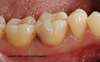

Après

Molaire cariée après onlay

Dent après pose onlay